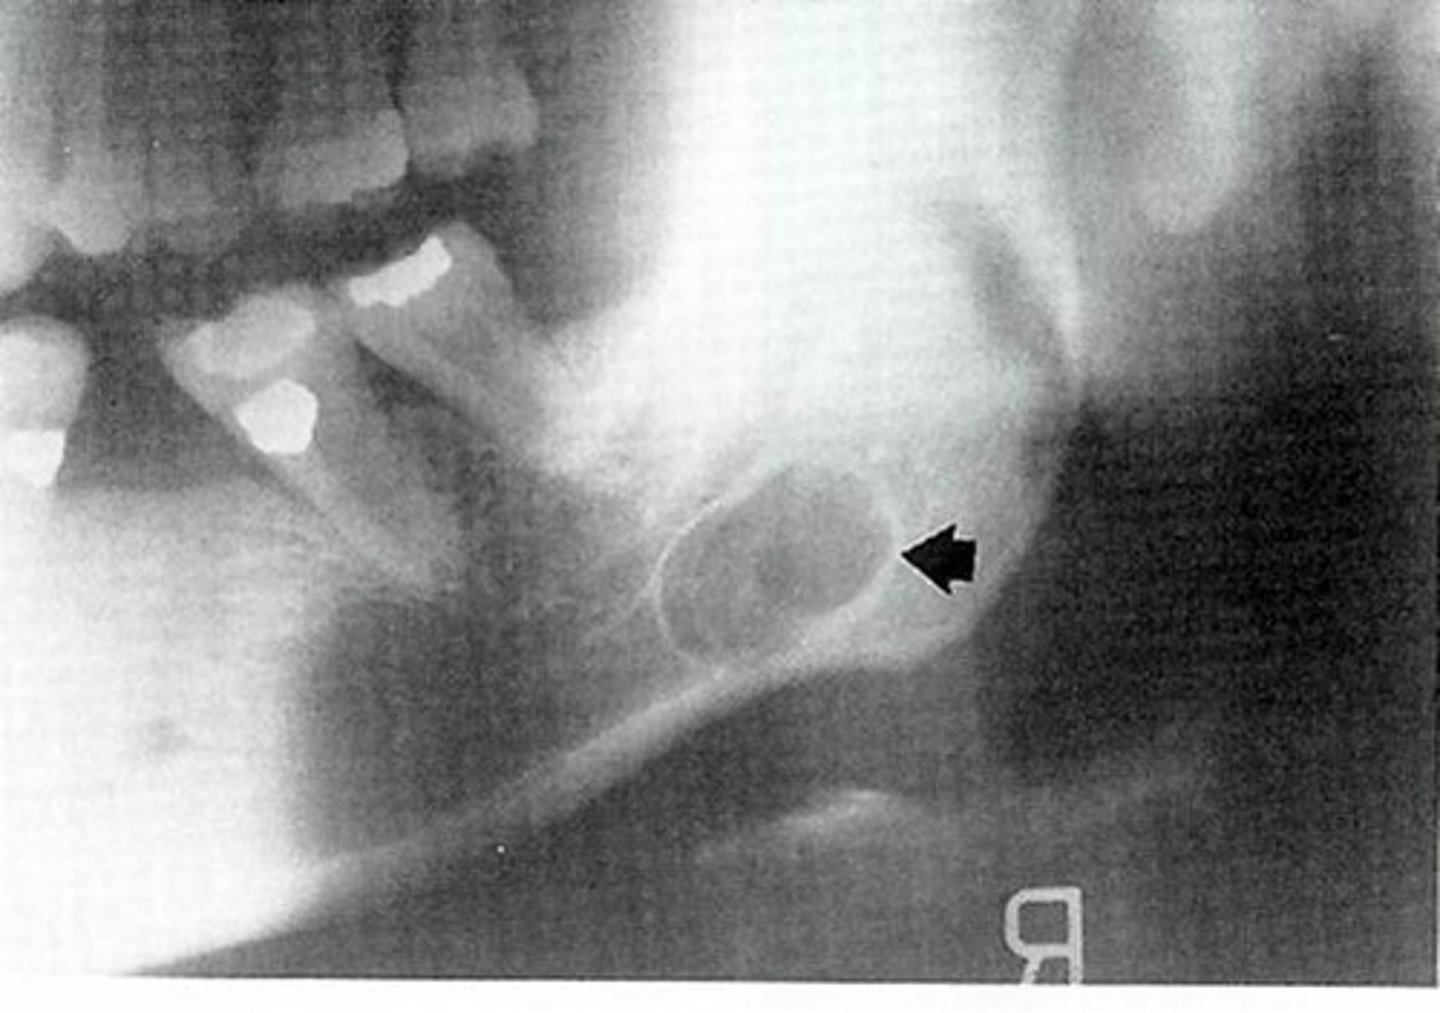

What are radiographic features of stafne bone cysts?

well-defined cyst-like radiolucency

1. anterior to angle of mand & inferior to mandibular canal

• unilateral or bilateral

radiolucent intraosseous lesion that is NOT lined with epitheium = NOT A TRUE CYST! **KNOW for exam

• also called Static Bone Cyst and Stafne Defect

developmental concavity containing normal salivary tissue on lingual aspect of posterior mandible

**KNOW FOR EXAM